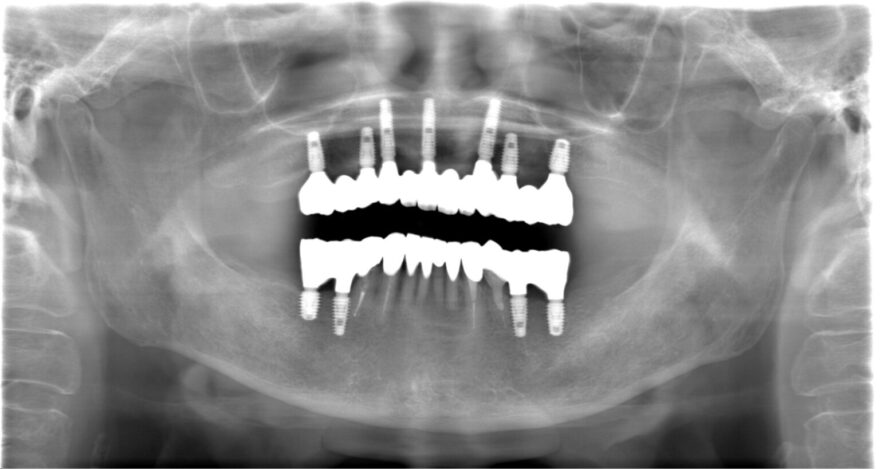

治療後のレントゲン写真

・上顎に7本のインプラント

・下顎に4本のインプラント

・前歯4本のセラミック修復

で快適な噛み合わせを再建する計画を立て、9カ月で全ての治療が終了しました。

治療中は使っていた入れ歯も使用して頂くので、歯が無い期間はありません。